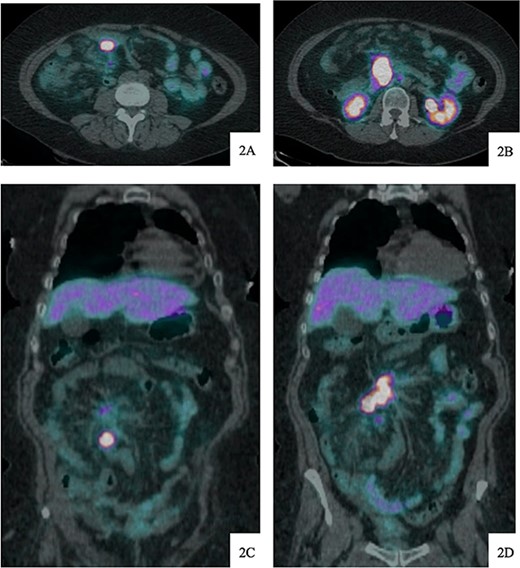

DOTATATE positron emission tomography-computed tomography scan at time of diagnosis in November 2017 revealed a small bowel primary tumor in the right lower quadrant consistent with terminal ileum (A) as well as the periduodenal mass near the root of the mesentery (B). Coronal reformatting redemonstrates the primary tumor (C) and mesenteric mass (D).